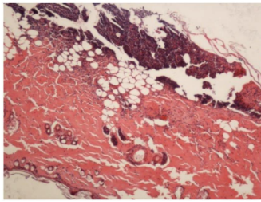

由皮肤病理切片可知,正常组大鼠皮肤组织完整,皮肤附属器清晰可见。造模24h后大鼠皮肤表皮脱落,真皮层结缔组织坏死,有明显的水肿现象,未见皮肤附属器。

造模10d 后模型组大鼠皮肤组织中出现疤痕组织,可见大量的淋巴细胞、浆细胞等炎症细胞。